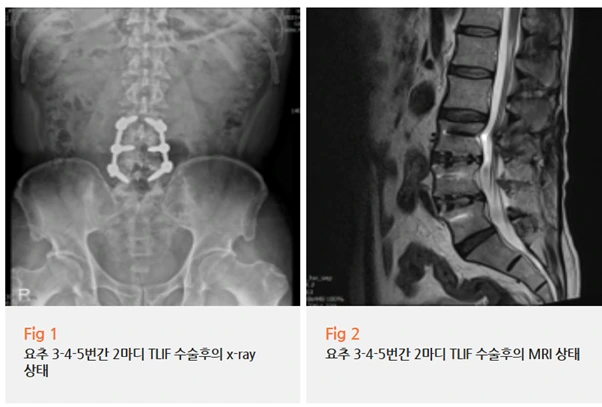

이미 다른 병원에서 척추 수술을 두 번이나 받으셨대요.

첫 번째 수술 후에도 통증이 계속되어서

두 번째로 척추유합술까지 하셨다고 하더라고요.

척추유합술이면

뼈와 뼈를 금속으로 고정하는 큰 수술이잖아요.

일단 정확한 상태 확인을 위해 MRI부터 찍어봤어요.

수술로 넣은 금속 삽입물은 잘 유지되고 있었고,

구조적으로는 큰 문제가 없어 보였어요.

물론 요추 4-5번과 천추 1번 부위에

만성 신경뿌리병증 소견이 있긴 했지만

이 정도 소견으로 환자분이 호소하시는 극심한 통증을

모두 설명하기엔 뭔가 부족했어요.